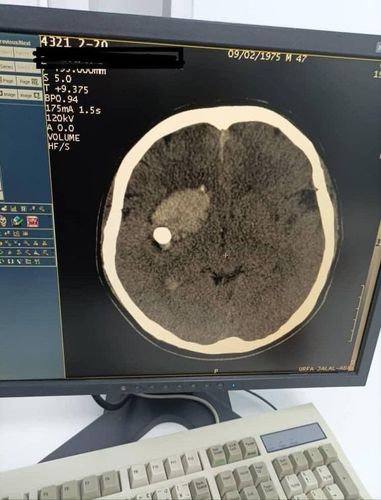

Neurosurgeons of the Jalal-Abad Regional Clinical Hospital performed an emergency complex brain surgery. Press center of the Ministry of Health of Kyrgyzstan reported.

The patient was admitted with an open penetrating wound to the head — the bullet was in the frontotemporal lobe on the right.

«Thanks to the Candidate of Medical Sciences, head of the Neurosurgical Department of the Regional Hospital Abdibayit Idirisov and his team, the patient was saved. The operation was successful, the postoperative condition of the patient is assessed as stable,» the Ministry of Health noted.